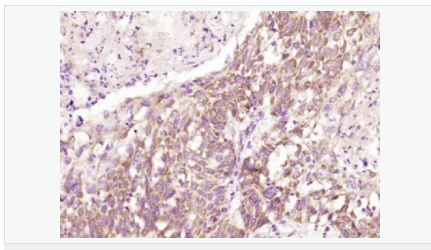

產品應用WB=1:500-2000 ELISA=1:5000-10000 IHC-P=1:100-500 IHC-F=1:100-500 ICC=1:100-500 IF=1:100-500 (石蠟切片需做抗原修復)

免 疫 原KLH conjugated synthetic peptide derived from human TEM8:201-300/564 <Extracellular>

Detected in umbilical vein endothelial cells (at protein level). Highly expressed in tumor endothelial cells.